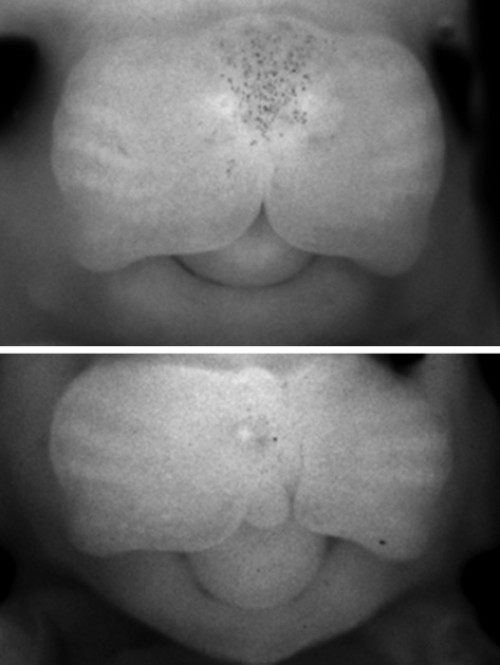

唇腭裂是一種最常見的出生缺陷,可以唇裂或腭裂其中一種形式單獨(dú)出現(xiàn),也可以唇裂和腭裂兩種形式共同出現(xiàn)。它們也能夠與其它畸形一起發(fā)生,形成一種綜合癥。根據(jù)《人的基因序列變化與人體疾病表征》,共有超過350種具有不同臨床表現(xiàn)的唇腭裂綜合征,而且大約每500到1000名新生兒中就有一例出現(xiàn)。唇裂,伴有或不伴有腭裂(CL/P),都是人類常見的一種先天性畸形。自古就有,而用自從開始在人類中出現(xiàn),就會(huì)附會(huì)以不同的解釋。其中的一些是經(jīng)驗(yàn)的積累,另外是關(guān)于其發(fā)生的猜測??偟膩碚f, 不具備分子生物學(xué)或者是基因解碼知識(shí)的人,即使是臨床醫(yī)生,也會(huì)認(rèn)為唇腭裂與基因無關(guān),但是基因解碼是一種比基因檢測更為先進(jìn)的理解基因作用的知識(shí)和技術(shù)體系,更清楚地揭示這種畸形是基因的作用方式發(fā)生異常的結(jié)果。

唇腭裂是一個(gè)通俗的說法,它是指在人的是唇和顎部有裂口。其實(shí)這個(gè)名稱并不能代表顱面部全部先天畸形。還包括牙槽突裂,另外還有有效性的唇裂還包括鼻底的裂開。再有由于牙槽突裂的存在,還會(huì)導(dǎo)致牙齒在發(fā)育當(dāng)中的一個(gè)畸形。這種畸形它會(huì)影響到口腔和面部的很多的器官和功能。另外由于腭裂存在,還會(huì)影響到患者的聽力。因此唇腭裂畸形是系統(tǒng)性、可能會(huì)影響多個(gè)方面的病變。這種病變一般來說是由于在發(fā)育過程中,由某種因素而導(dǎo)致形成口腔和面部發(fā)育的一些生發(fā)中心沒有正常的連接和融合所導(dǎo)致的。唇腭裂是一種非常常見的先天的頜面部的發(fā)育畸形,一般來說在正常人群里面就達(dá)到1-2‰。亞州人群高于非洲人群?;蛘呤?00-700個(gè)人當(dāng)中就會(huì)有一個(gè)唇腭裂小孩的發(fā)生。這種唇腭裂會(huì)在妊娠前的前三個(gè)月就出現(xiàn),由于各種各樣的因素,而影響胚胎的發(fā)育。這種畸形會(huì)影響到我們小朋友,除了形態(tài)和功能以外,它的影響還是非常深遠(yuǎn)。包括未來的發(fā)音,還有頜面部骨骼的發(fā)育,還有外形和功能的一些畸形和不正常。還有可能會(huì)影響到他參與社會(huì)行為,一些社會(huì)交往,反過來還會(huì)影響他的心理發(fā)育。因此這種唇腭裂的畸形是需要我們特別關(guān)注的。在胚胎發(fā)育的早期,唇、腭是由兩側(cè)組織往身體中線融合起來的,若不能正常融合,就會(huì)產(chǎn)生各種不同部位的裂縫,單純嘴唇裂開,稱為唇裂,既有唇部裂開又有腭部裂開稱為唇腭裂,有時(shí)僅口腔內(nèi)腭部裂開而外部正常,則稱為腭裂。